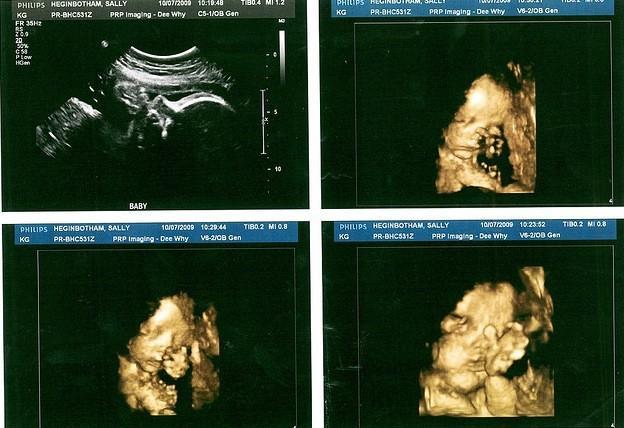

De vez en cuando salen a la luz ecografías curiosas que nos muestran algún gesto del bebé, especialmente si vemos una grabación, y es que en el útero el bebé no deja de moverse y de gesticular. Un estudio reciente nos muestra cuáles son los gestos más frecuentes del bebé en el vientre materno.

El estudio, titulado "4D ultrasound evaluation of fetal facial expressions during the latter stages of the second trimester" ("Evaluación a través de ecografías 4D de la expresión facial fetal durante las últimas estapas del segundo trimestre") ha sido publicado en el International Journal of Obstetrics and Gynaecology.

Se grabó durante 15 minutos seguidos, a través de la técnica del ultrasonido 4D, a 24 fetos sanos de 25 a 27 semanas de embarazo. Las frecuencias de los distintos gestos (articular, sacar la lengua, bostezar, succionar, parpadear, fruncir el ceño, y sonreír) se compararon con las observadas a los 28-34 semanas de gestación en un estudio anterior.

Foto | Aidan-Sally en Flickr-CC Más información | International Journal of Obstetrics and Gynaecology En Bebés y más | Ecografías en 2D, 3D y 4D, ¿Qué tipo de ecografía es mejor?, El bebé que dijo OK en su ecografía